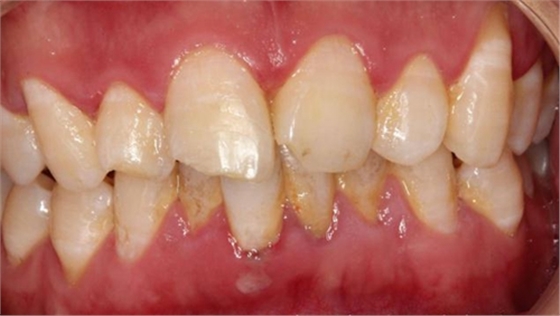

最后附一例樹(shù)脂關(guān)閉牙間隙的病例。具體操作不做詳細(xì)描述。

術(shù)前如下: